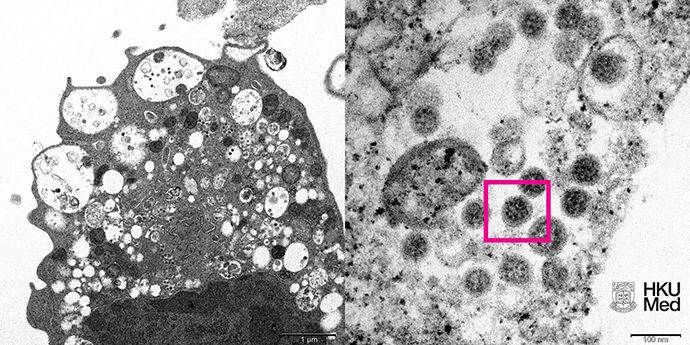

▲香港大學公布的Omicron變種病毒顯微鏡下成像。(圖/翻攝澎湃新聞)

香港大學今(8)日發布新冠變種病毒Omicron在顯微鏡下的真實面貌,分別為低倍電子顯微鏡所呈現的感染新型冠狀病毒Omicron變種毒株後的猴腎細胞(Vero E6)及高倍電子顯微鏡下受感染的Vero E6細胞。此外,港大在1日也率先成功從臨床標本中分離出Omicron病毒,成為亞洲首個揭開該病毒神秘面紗的團隊。

《澎湃新聞》報導,根據港大公布的照片顯示,圖左照片為低倍電子顯微鏡下感染新型冠狀病毒奧密克戎(Omicron)變異株後的猴腎細胞(Vero E6)。照片顯示細胞受損,腫脹囊泡,囊泡內含有黑色小病毒顆粒。顯示細胞受損,腫脹囊泡,囊泡內含有黑色小病毒顆粒。

圖右照片則為高倍電子顯微鏡下受感染的Vero E6細胞。照片顯示病毒顆粒表面呈現皇冠形的刺突蛋白(紅框處)。